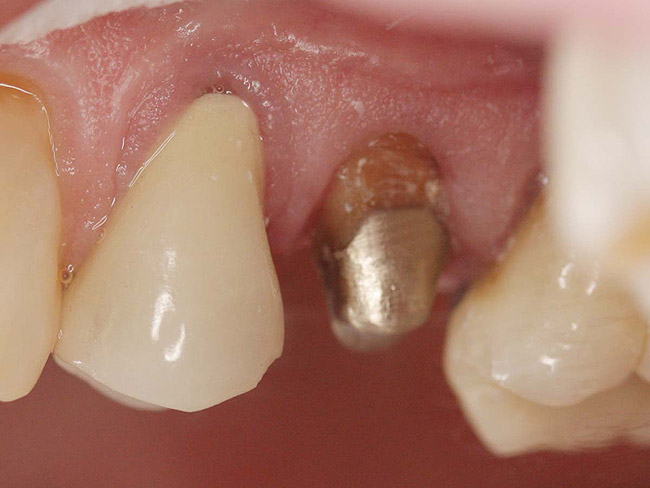

Case 1

A Class IN maxillary bicuspid was previously restored with a fiber post and an all-porcelain crown (Figure 1). The forces of the oral environment resulted in fracture of the fiber post and crown failure. The remaining fiber post in the root was removed, and anti-rotational areas were prepared for a cast post (Figure 2). A gold cast post was constructed at a dental laboratory, using an indirect technique (Figure 3). A porcelain-fused-to-metal (PFM) crown was constructed with a bevel finish to provide a ferrule and reduce forces on the post (Figure 4 and Figure 5).

Figure 2  Same second bicuspid as Figure 1 after removal of the fractured fiber post.

Figure 2

Figure 3  Cast post to restore the second bicuspid.

Figure 3